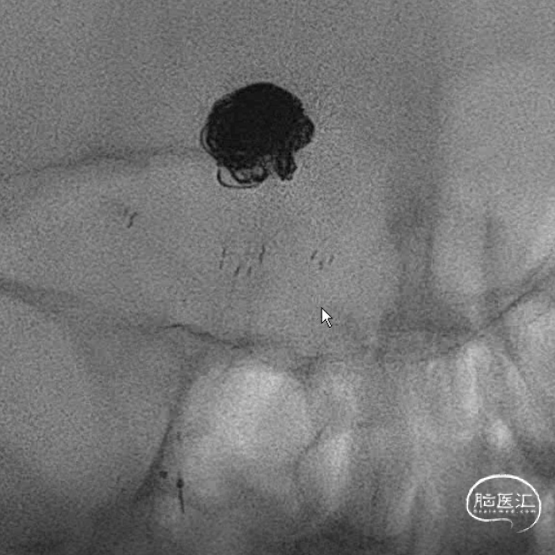

连续填了两枚圈,微导管头没变,但是开始左右摆圈。不好,根据以往经验,瘤顶偏右侧的空间要丢掉机会,如果再填一个圈,即将把动脉瘤颈部偏右侧大脑后动脉部分填致密,这样的话残留在瘤顶部的空白处可能填不上,因此直接采取下一方案。于是趁着瘤颈还有空间,将右侧支架导管撤下,将头塑型为指头或单弯,穿支架网孔到位。

这是微导管到位就放心了,但是一定注意,穿网孔微导管可能有阶梯效应,使其弹射,因此一定要控制好张力,减少戳破动脉瘤的风险。

管他如何,先填个圈把这一部分添上。接下来就是考虑把动脉瘤偏左侧进行正常填塞。

动脉瘤右侧是没事了,但是左侧好像失策了,可以看到左侧部分有一部分圈,但是还是不太致密,但是由于弹簧圈微导管由于在填弹簧圈时,不断减张力,因此已经离开了原来计划的位置。千算万算,好像还是忽略了这一点。